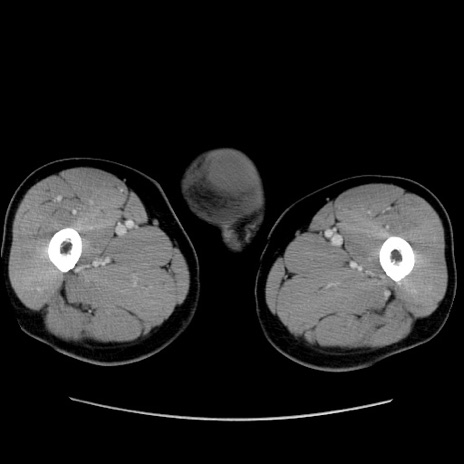

症例34(横断像)

【症例】60歳代 男性

【主訴】右鼠径部膨隆

【現病歴】1年程前より右鼠径部膨隆あり。自己にて還納可能だったため放置していた。3時間前より右鼠径部の脱出を認め、還納困難となり受診。

【既往歴】高血圧

【身体所見】右鼠径部に小児頭大の膨隆あり。弾性硬であり、用手還納は困難。左鼠径部にも膨隆を認める。脱出はなし。

【データ】WBC 15500、CRP 測定なし